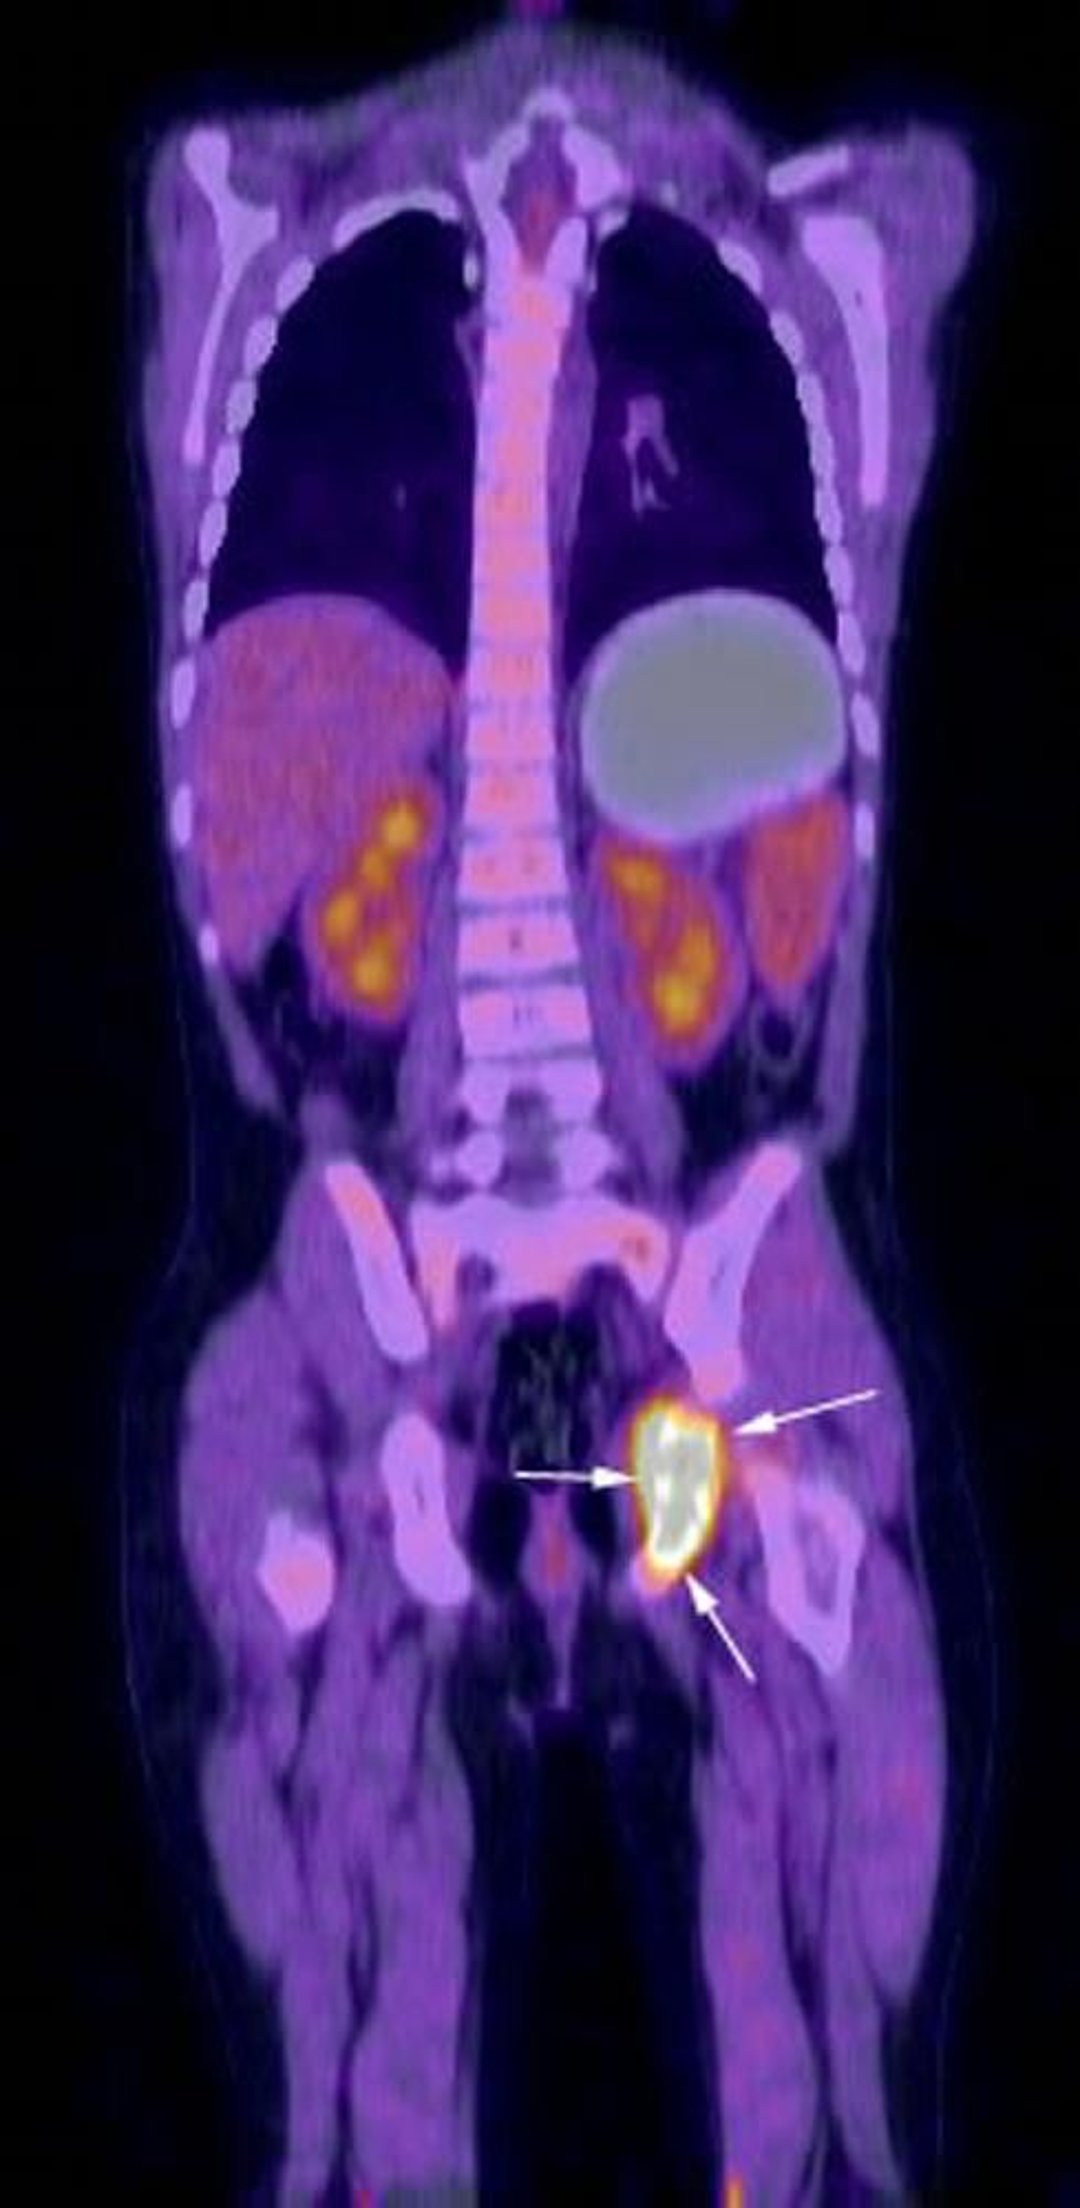

Das koronale Rekonstruktionsbild der FDG-PET-CT-Untersuchung zeigt eine intensive Stoffwechselaktivität im Bereich des linken Sitzbeins (Pfeile), die der bekannten Langerhans-Zell-Histiozytose des Patienten entspricht.

Image courtesy of Hakan Ilaslan, MD.